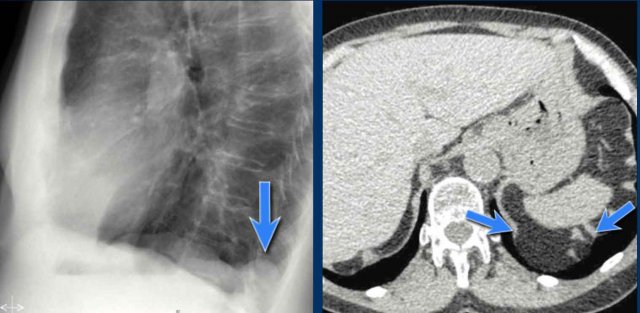

On the PA chest radiograph, a lateral displacement of the azygoesophageal line can be seen.

It is caused by a hiatal hernia.

The arrow points to the barium contrast within the hiatal hernia.